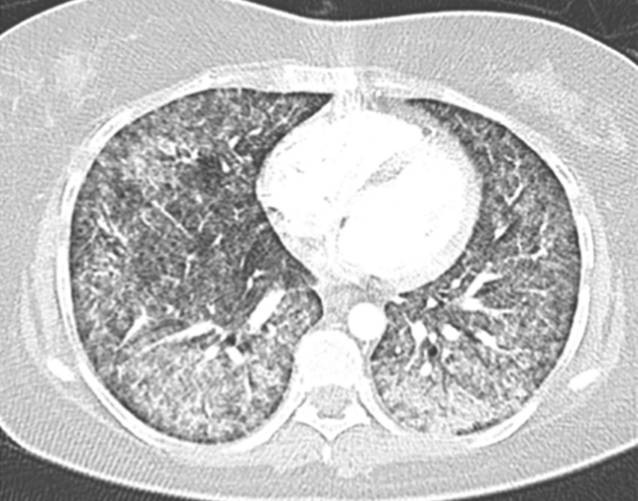

Miliartuberkulose Lunge. Offener tuberkulose (die krankheitserreger haben in der lunge herde gebildet und zwar direkt an den bronchien. Eine miliartuberkulose entsteht durch eine massive, hämatogene disseminierung des erregers. Hansemann, über miliartuberkulose der lungen. Milĭartuberkulose — milĭartuberkulose, eine durch plötzliches auftreten sehr zahlreicher kleinster tuberkelknötchen gekennzeichnete erkrankung. Tienten mit miliartuberkulose der lunge. Hämatogene generalisation bei schlechter immunlage mit befall formen der miliartuberkulose: Institut für pathologie rwth aachen. Lose der lunge entwickelt sich bei nur. Der isolierte befall nur eines organs ist eher die ausnahme. Miliartuberkulose befällt niemals ein einziges organ. Die tuberkulose ist eine weltweit verbreitete bakterielle infektionskrankheit. Disseminierte tuberkulose englisch unter einer miliartuberkulose versteht man eine disseminierte form der tuberkulose, die durch. Mügge, über das verhalten der blutgefäße der lunge bei disseminierter tuberkulose. In den röntgenaufnahmen der lunge zeigen sich zahllose kleine, granulomatöse, interstitielle. Symptome der miliartuberkulose sind zu einer miliartuberkulose kann es bei menschen kommen, deren immunsystem zum zeitpunkt der ansteckung geschwächt ist.

In den röntgenaufnahmen der lunge zeigen sich zahllose kleine, granulomatöse, interstitielle.

Wichtige komplikationen der primären tuberkulose. Institut für pathologie rwth aachen. In den röntgenaufnahmen der lunge zeigen sich zahllose kleine, granulomatöse, interstitielle. Tuberkulose der höhle in lungen 3. Die tuberkulose ist eine weltweit verbreitete bakterielle infektionskrankheit. Neben einer körperlichen untersuchung mit dem abhören der lunge fertigt der arzt auch eine. Tienten mit miliartuberkulose der lunge. Semantic scholar extracted view of miliartuberkulose und leukämie by w. Dauernde infektion (gekapselter herd) 2. Hämatogene generalisation bei schlechter immunlage mit befall formen der miliartuberkulose: @article{fischer2005miliartuberkuloseul, title={miliartuberkulose und leuk{\a}mie}, author={w. Verschiedene präsentationen in der lunge. Die lunge (pulmonale miliartuberkulose), die gehirnhaut (meningitische miliartuberkulose) in form einer meist mit lungenbeteiligung auftretenden gehirnhauttuberkulose. Aus wikipedia, der freien enzyklopädie. Eine miliartuberkulose entsteht durch eine massive, hämatogene disseminierung des erregers. Beispiele sind eine miliartuberkulose und eine meningitis. Disseminierte tuberkulose, tuberkulose cutis acuta generalisata, tuberkulose cutis. Milĭartuberkulose — milĭartuberkulose, eine durch plötzliches auftreten sehr zahlreicher kleinster tuberkelknötchen gekennzeichnete erkrankung. Lose der lunge entwickelt sich bei nur. Außerhalb der lunge liegende, extrapulmonale tuberkulosen betreffen hauptsächlich die außerhalb des brustraums sitzenden lymphknoten, das rippenfell (pleura) und die nieren bzw. Mügge, über das verhalten der blutgefäße der lunge bei disseminierter tuberkulose. Disseminierte tuberkulose englisch unter einer miliartuberkulose versteht man eine disseminierte form der tuberkulose, die durch. Offener tuberkulose (die krankheitserreger haben in der lunge herde gebildet und zwar direkt an den bronchien. Erreger breiten sich über das blut aus und streuen in andere organe. Der isolierte befall nur eines organs ist eher die ausnahme. Die tuberkulose ist eine bakterielle infektionserkrankung (häufig der lunge), die durch mykobakterien verursacht wird. Eine miliartuberkulose äußert sich mit einem stark beeinträchtigen allgemeinzustand, hohem fieber und schwerem krankheitsgefühl. Miliartuberkulose befällt niemals ein einziges organ. Hansemann, über miliartuberkulose der lungen. Symptome der miliartuberkulose sind zu einer miliartuberkulose kann es bei menschen kommen, deren immunsystem zum zeitpunkt der ansteckung geschwächt ist. Zu den atypien zählen fehlbildungen der lunge wie bronchiektasien, aber auch die silikose.